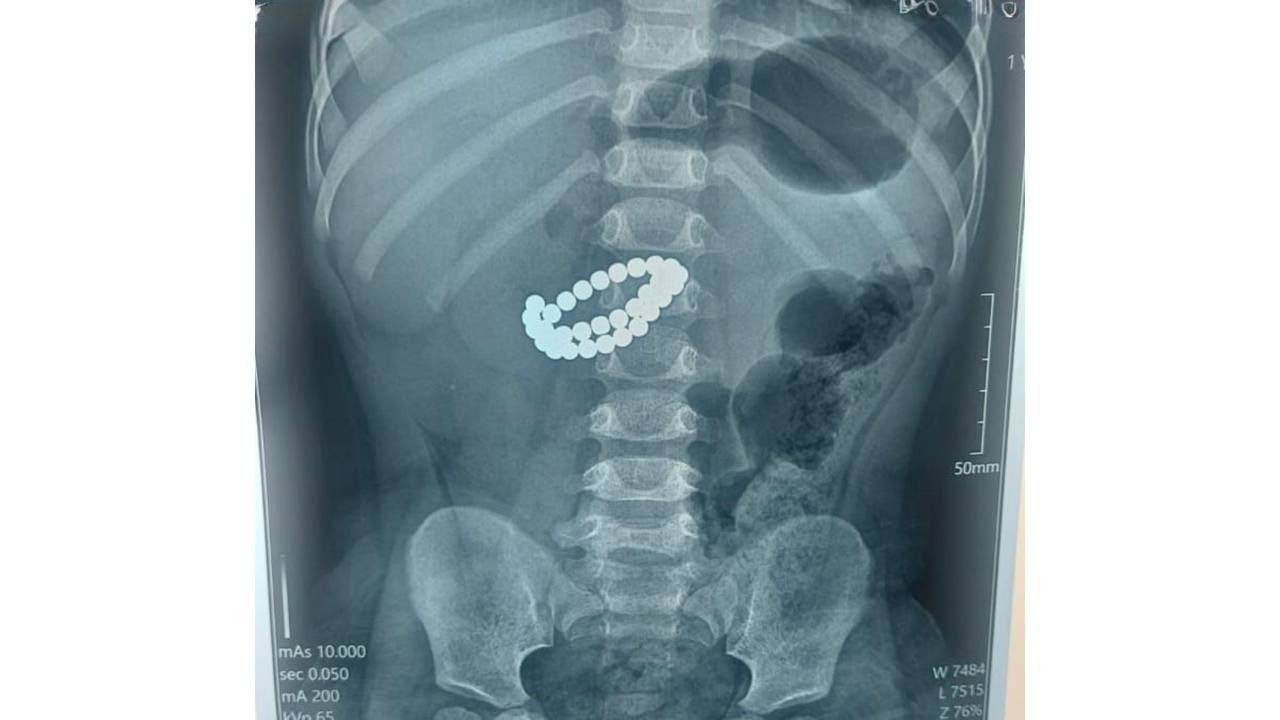

1 жас 9 айлық бүлдіршін аурухананың қабылдау бөліміне өте ауыр халде жеткізілген. Тексеру кезінде оның ішегінен бір-біріне жабысып қалған 31 магнит анықталды. Дәрігерлер дереу «аш ішектің көптеген жерден тесілуі» және «жайылмалы нәжісті перитонит» (іш пердесінің жедел қабынуы) деген диагноз қойған.

Фото: Әлеуметтік желіден